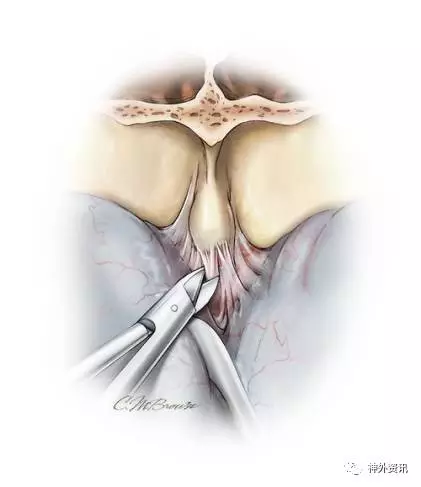

图12. 如果术者希望通过双额入路抵达完全位于硬膜内的肿瘤,比如脑膜瘤,于平行骨缘方向切开硬脑膜(A和B)。上矢状窦前部用0号丝线间断结扎,然后离断。尽管矢状窦旁前部的桥静脉被认为是不重要的,但术者在牺牲它们的过程中仍要小心。吸引器头端清晰可见肿瘤组织(C)。缺损的硬脑膜采用一块颞肌筋膜瓣完全封闭,额窦利用骨膜瓣覆盖(D和E)。

在上矢状窦离断处切开大脑镰,将硬膜下垂部分反折至前方。如果需要额外的硬膜内手术通道,硬膜切开的侧方可以向后扩展直至获得做够的暴露视野。由于颈部的过伸,额叶由于重力的牵拉会远离前颅底,从而获得足够的手术通道。病变通过显微手术得到恰当的处